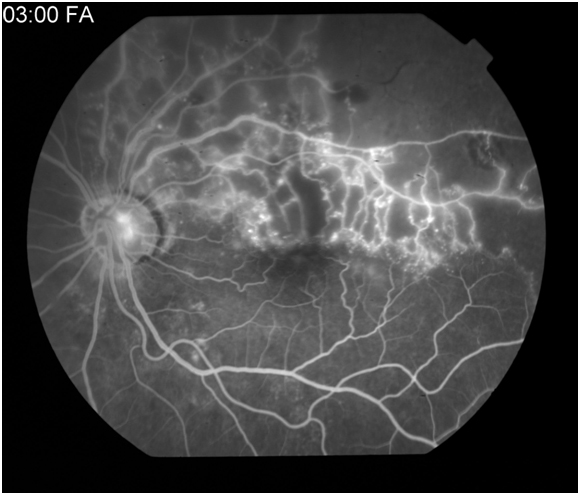

Figure 6A: Late arteriovenous or laminar venous phase angiogram in a patient with a superotemporal branch retinal vein occlusion. Hypofluorescence is noted along the superotemporal arcade secondary to capillary dropout. 6B: Late arteriovenous phase demonstrates leakage from the supertemporal retinal vessels.